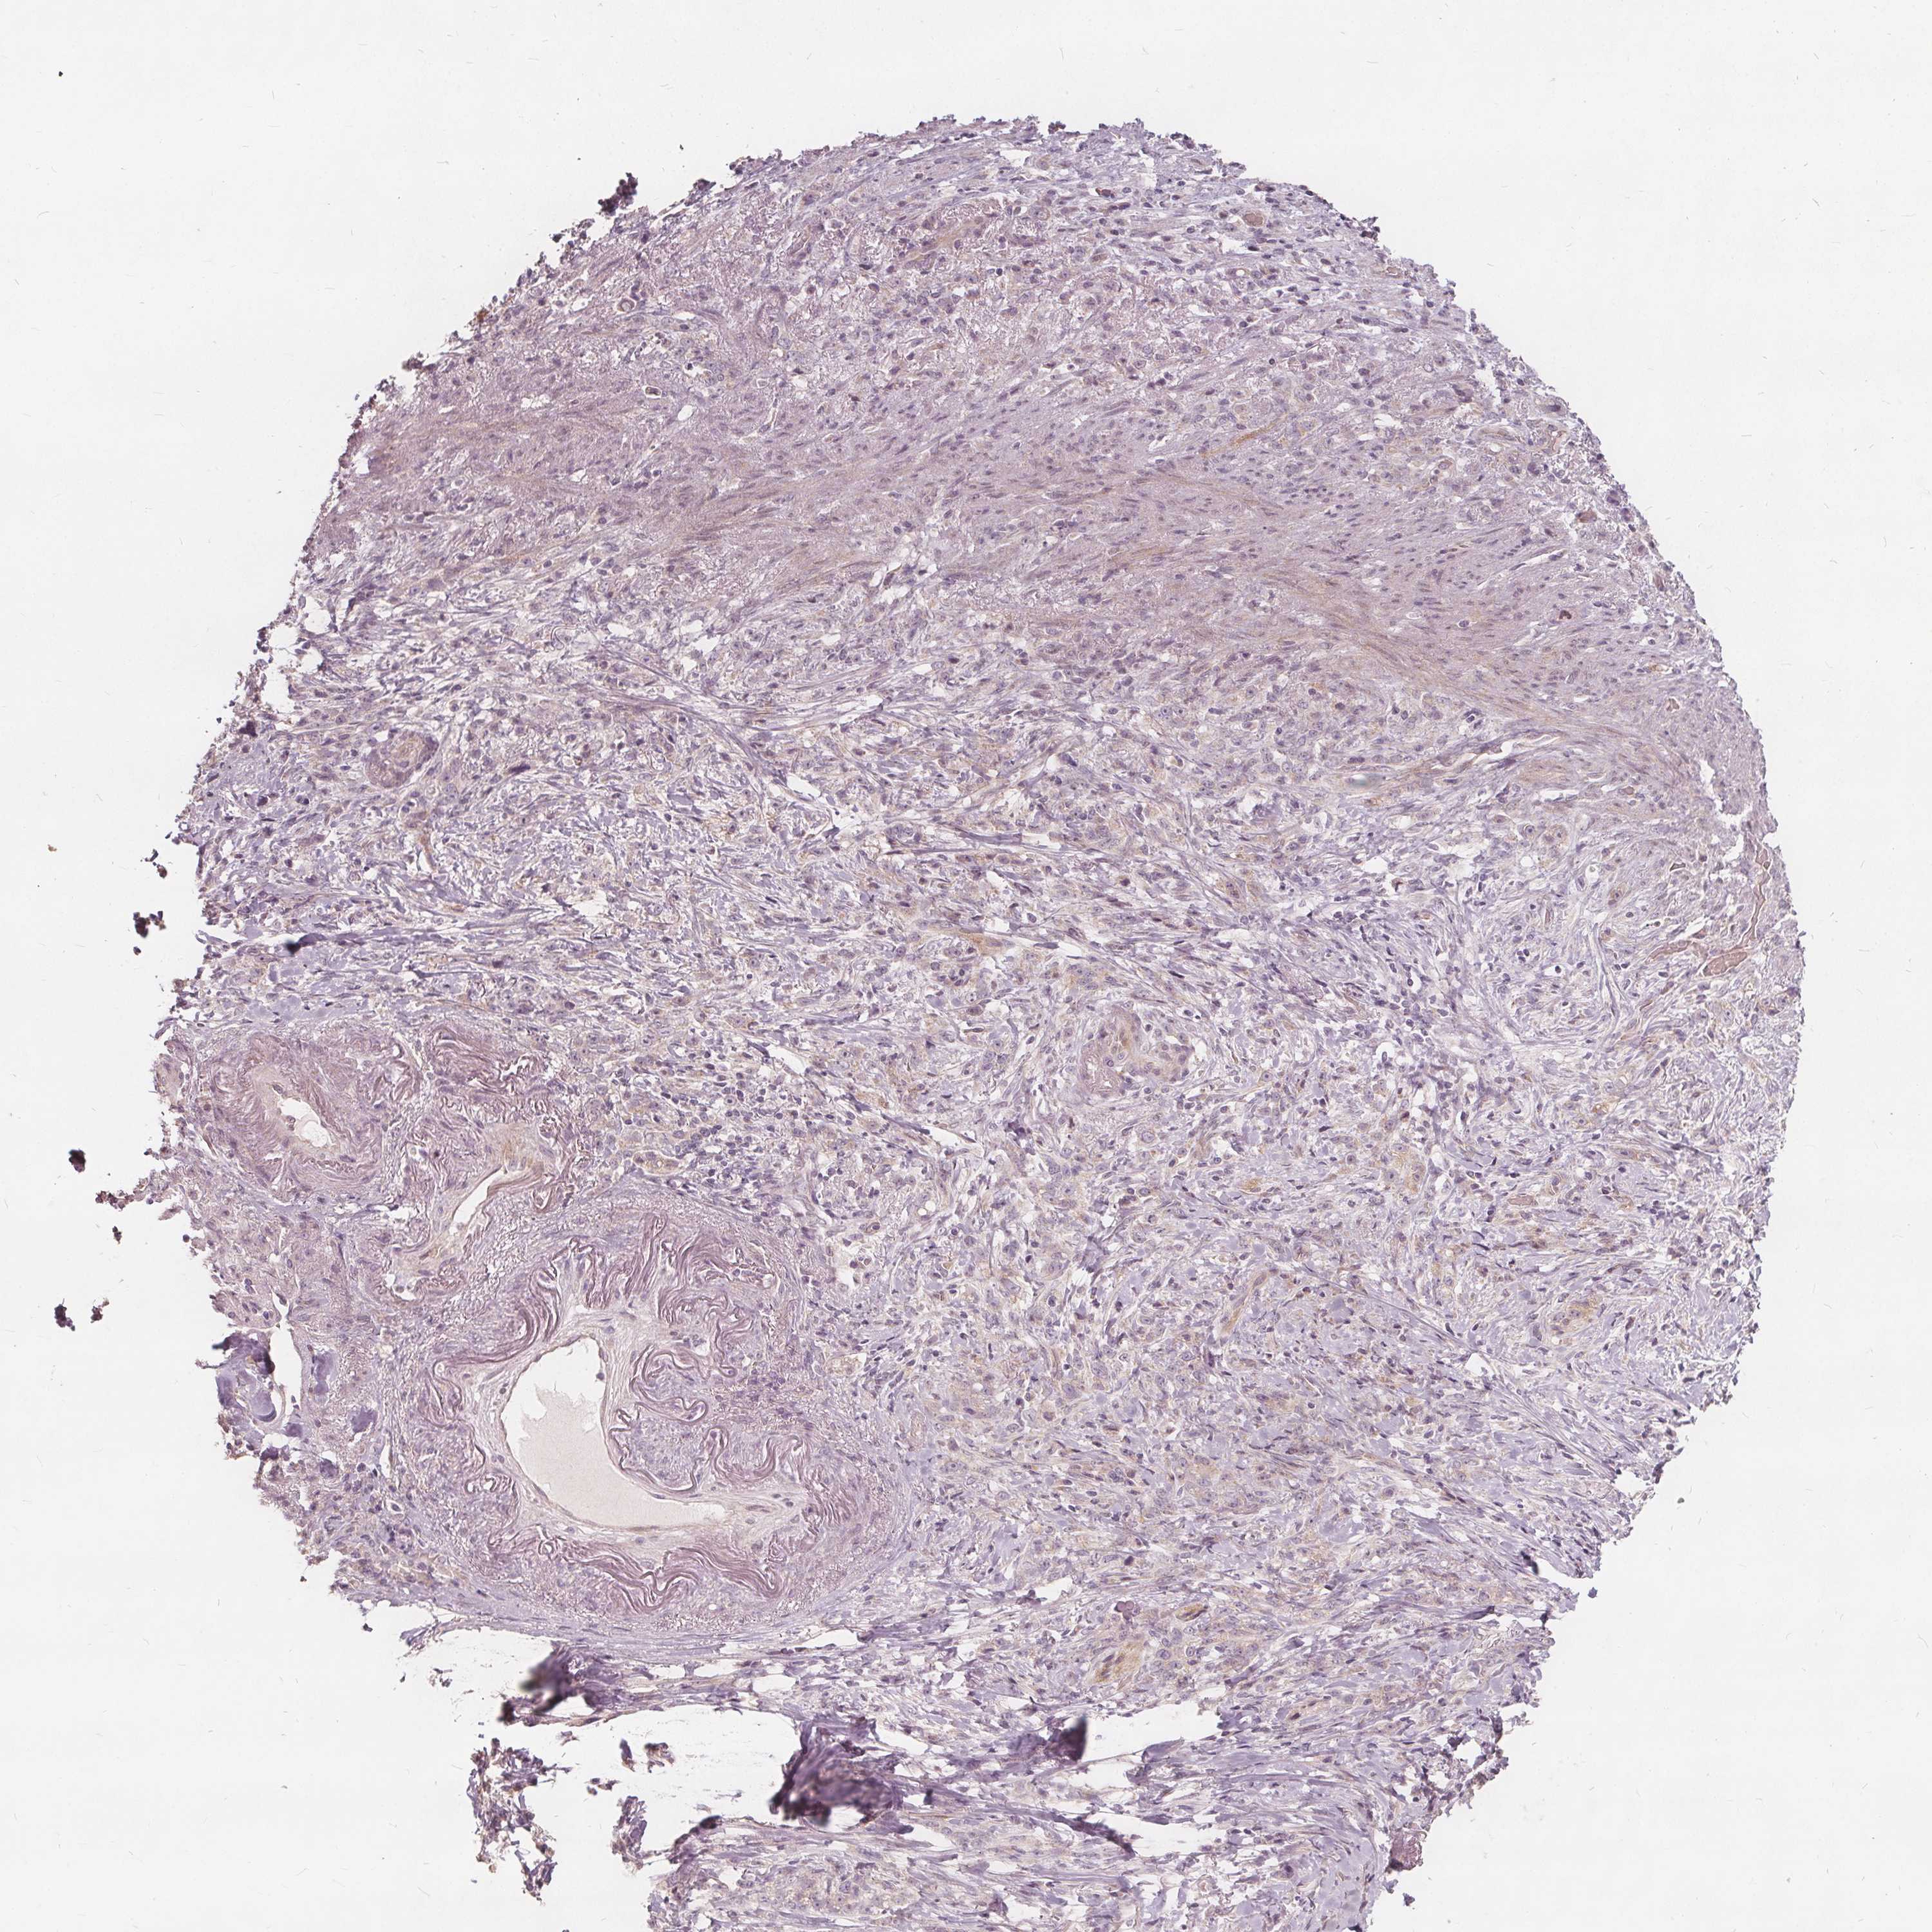

STOMACH CANCER - Protein expressioni

A mouse-over function shows sample information and annotation data. Click on an image to view it in a full screen mode. Samples can be filtered based on level of antibody staining by selecting one or several of the following categories: high, medium, low and not detected. The assay and annotation is described here.

Note that samples used for immunohistochemistry by the Human Protein Atlas do not correspond to samples in the TCGA dataset.

Antibody stainingi

Antibody staining in the annotated cell types in the current human tissue is reported as not detected, low, medium, or high, based on conventional immunohistochemistry profiling in selected tissues. This score is based on the combination of the staining intensity and fraction of stained cells.

Each image is clickable and will lead to virtual microscopy that enables deeper exploration of all samples and also displays staining intensity scores, fraction scores and subcellular localization as well as patient and tissue information for each sample.

Antibody HPA017336

Antibody CAB069423

Adenocarcinoma, NOS